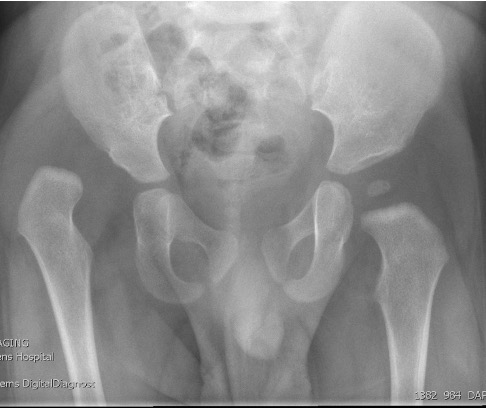

Xray

Dislocated hips in the setting of DDH with ncreased acetabular index